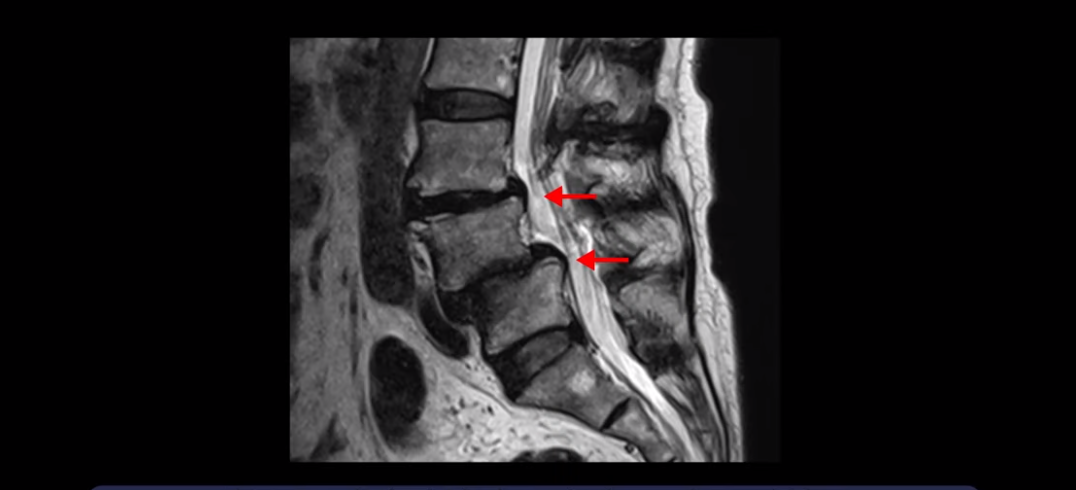

이분은 전방전위가 2단계로 매우 심하고,

신경 구멍도 두 마디나 좁아져있습니다.

전방전위와 협착이 다 심하니까 대학병원에서 나사 6개를 박는 유합술을 권유 받으셨는데요. 그런데 이분이 처음 아프게 된 건 작년 10월인데, 이분이 만약 아프기 전인 작년 초에 MRI를 찍었다면 지금의 MRI와 많이 다를까요? 아닙니다. 거의 차이가 없을 겁니다. 이미 척추 뼈는 많이 밀려나가 있고 신경 구멍은 똑같이 좁아진 상태였을 겁니다. 그 상태로도 전혀 안 아프게 아주 오랫동안 사신 겁니다. 그러다가 작년 10월에 무리한 일과 운동 때문에 허리 근육에 문제가 생기면서 신경이 눌리기 시작한 겁니다. 만일 아프지 않을 때 MRI를 찍고 척추 뼈가 밀려나가고 신경이 눌렸으니까 나사 박는 수술을 하자고 하면, 수술을 받을 사람이 있을까요?